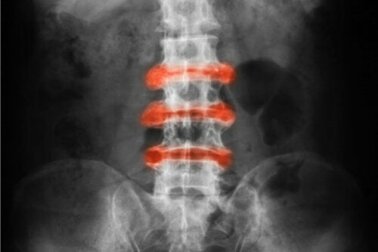

Afinal, que doença é essa? É definida como uma artrite inflamatória localizada principalmente nas articulações das costas e da pelve. As dores agudas e a rigidez tendem a apresentar melhora com atividades físicas e, de fato, a inatividade complica o quadro.

- Espondiloartrite anquilosante: artrite inflamatória com maior incidência na coluna vertebral.